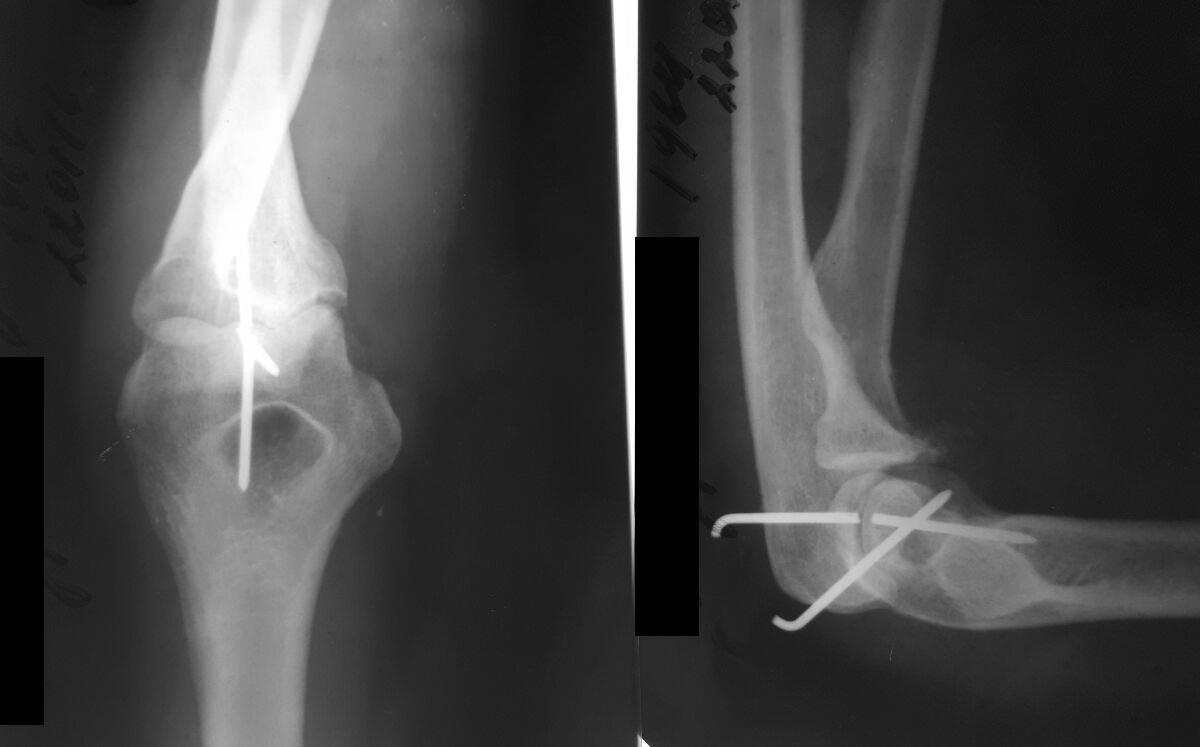

Доброго времени суток, уважаемые коллеги. Женщина 47лет. Три недели назад произведено открытое вправление по поводу застарелого вывиха предплечья.

Фиксировано двумя спицами. Сейчас обратилась для удаления спиц и проведения ЛФК.На рентген контроле выявлен перелом спицы. Посоветуйте, как ее теперь удалить.

Можно сделать КТ. Если кончик спицы полностью погружен в кость и не проходит через локтевую ямку - бог с ним. Если торчит настолько, что можно захватить кончиком зажима - удалить под рентгенотелевизионным контролем слегка расширив отверстие от удаленного второго отломка спицы. А если торчит совсем чуть-чуть - втолкнуть дальше в кость тупым кончиком спицы через отверстие от удаленного второго отломка.

Задний доступ. Трепанация локтевой ямки. После операции сразу начать движения.